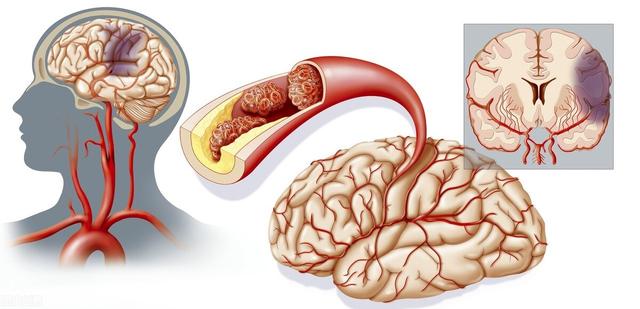

Notre cerveau gère presque toutes les fonctions de notre corps et est connu comme le commandant du corps. Le cerveau dépend du sang pour transporter l'oxygène et les nutriments dont il a besoin. Lorsque les vaisseaux sanguins sont bloqués pour diverses raisons, le cerveau est incapable d'obtenir de l'oxygène et des nutriments et meurt, entraînant la perte de fonctions de notre corps, ce qui est appelé infarctus cérébral. Les fonctions des différentes parties du cerveau étant différentes, les patients auront des séquelles plus ou moins importantes selon la localisation et l'étendue de la nécrose. Certaines personnes peuvent n'avoir qu'un léger vertige et découvrir qu'elles ont subi un infarctus cérébral lorsqu'elles se rendent à l'hôpital pour un examen (la plupart des patients atteints d'infarctus cérébral lacunaire sont découverts au cours de l'examen). Certains patients garderont des séquelles telles que l'hémiplégie, l'immobilité, la cécité, le retard mental, voire la mort.

L'infarctus cérébral est en fait un trouble de l'irrigation sanguine des vaisseaux sanguins du cerveau, qui se traduit par une irrigation sanguine insuffisante du cerveau, ce qui déclenche l'ischémie et l'hypoxie et aggrave encore la nécrose ischémique ou le ramollissement du tissu cérébral. L'infarctus cérébral représente la majorité des accidents vasculaires cérébraux dans la pratique clinique, et les types d'accidents vasculaires cérébraux les plus courants sont les suivantsThrombose cérébrale, infarctus lacunaire et embolie cérébraleetc.

L'infarctus cérébral est divisé en plusieurs types en fonction des différentes causes de l'infarctus : la rupture de la plaque causée par l'athérosclérose, formant un thrombus qui bloque les vaisseaux sanguins cérébraux, forme un infarctus cérébral ; l'embolie formée dans la région du cœur en raison d'une fibrillation auriculaire, d'un flutter auriculaire, d'une insuffisance cardiaque, d'une maladie valvulaire cardiaque, etc., qui pénètre dans les vaisseaux sanguins cérébraux avec le flux sanguin pour bloquer les vaisseaux sanguins cérébraux, forme également un infarctus cérébral ; l'occlusion des petits vaisseaux sanguins des artères cérébrales en raison d'un durcissement et de lésions, etc. forme également un infarctus cérébral, et ces infarctus cérébraux se produisent lentement en termes de pathogenèse. Ces infarctus cérébraux, bien qu'ils soient lents à se produire, mais lorsque les vaisseaux sanguins cérébraux sont soudainement bloqués, en particulier les vaisseaux sanguins importants responsables de l'approvisionnement en sang du cerveau, l'infarctus cérébral se produit d'un seul coup et il n'y a pas trop de précurseurs pour que nous puissions y faire face. L'infarctus cérébral se produit directement lorsqu'il entraîne directement dans le corps une hémiplégie, une aphasie, une ataxie, qui peuvent être accompagnées de maux de tête sévères, de nausées, de vomissements et d'autres symptômes, et l'état peut rapidement évoluer vers un infarctus cérébral. Par conséquent, pour prévenir l'infarctus cérébral, nous devrions toujours contrôler activement le risque à partir de la pathogenèse, et l'idée de se fier aux précurseurs ou aux symptômes précoces pour juger du risque d'infarctus cérébral est très difficile à mettre en œuvre pour prévenir le risque et intervenir à l'avance.

Pour l'infarctus cérébral occlusif athéroscléreux et le petit infarctus artérioscléreux, il est particulièrement important de bien prévenir l'athérosclérose et de contrôler la stabilité de la plaque. Pour ralentir le processus d'athérosclérose et protéger la santé cardiovasculaire et cérébrovasculaire, il faut tout d'abord adopter un mode de vie sain et s'y tenir, suivre un régime alimentaire sain, faire de l'exercice physique de manière raisonnable, veiller à contrôler son poids, arrêter de fumer et de boire de l'alcool, avoir de bonnes habitudes de travail et de repos et veiller à maintenir un état d'esprit calme et optimiste, ce qui est très important pour protéger la santé artérielle et réduire le risque d'infarctus cérébral. Ces aspects sont très importants pour protéger la santé vasculaire artérielle et réduire le risque d'infarctus cérébral.

La pression artérielle et la glycémie doivent être contrôlées dans une fourchette raisonnable, les lipides doivent être strictement contrôlés. Pour les patients présentant un risque élevé d'infarctus cérébral, le taux de cholestérol LDL doit généralement être contrôlé à 1,8 ou moins, afin de mieux stabiliser les plaques et de retarder le développement de l'athérosclérose. Outre le contrôle des trois taux les plus élevés, les patients atteints d'athérosclérose sévère peuvent, pour prévenir le risque d'infarctus cérébral, prendre des médicaments antiplaquettaires, tels que l'aspirine, afin de réduire le risque de formation de thrombus lors de la rupture de la plaque.

L'infarctus cérébral est également appeléInfarctus cérébral ou accident vasculaire cérébral ischémique (AVC ischémique cérébral)Ce terme désigne la nécrose ou le ramollissement du tissu cérébral dû à un manque d'apport sanguin au cerveau, qui se produit à la suite d'une ischémie ou d'une hypoxie.

L'infarctus cérébral est une maladie du cerveau d'apparition soudaine qui peut survenir à tout âge. La gravité de la maladie est étroitement liée à la localisation et à la taille du caillot sanguin.Les patients d'âge moyen et les personnes âgées entre 45 et 70 ans constituent le principal groupe de patients qui développent la maladie.。